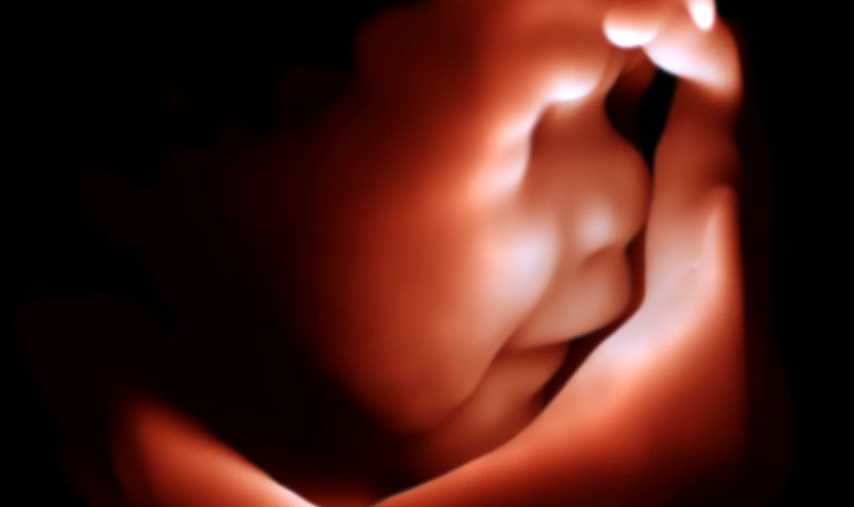

Es particularmente valioso en exámenes obstétricos, ya que permite a los ginecólogos controlar el progreso de los embarazos y evaluar el bienestar del feto. Las capacidades avanzadas de imágenes del escáner proporcionan imágenes detalladas del feto y ayudan a los ginecólogos a detectar posibles anomalías o complicaciones.

Las imágenes de alta resolución del escáner brindan a los ginecólogos información valiosa para un diagnóstico preciso y una planificación adecuada del tratamiento.